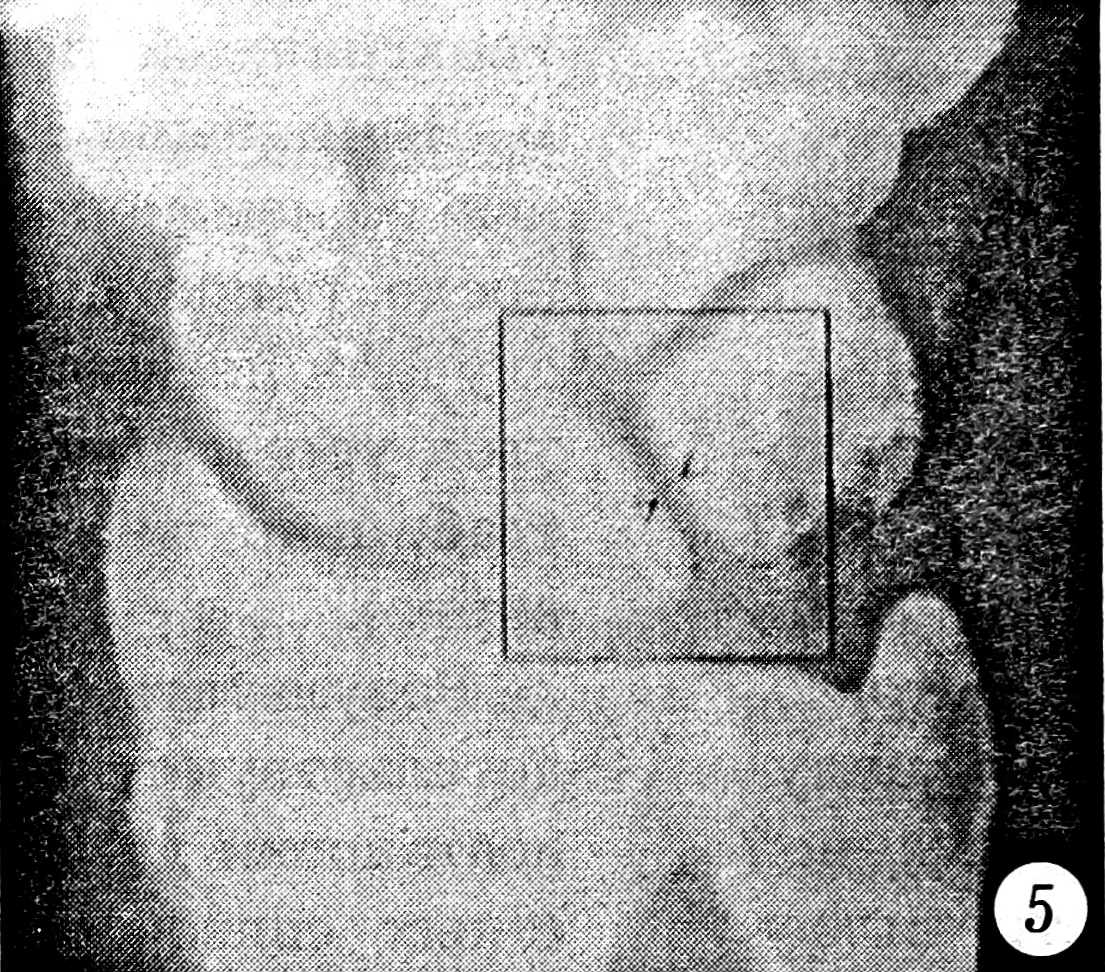

Исследовались первичные рентгенограммы и контрольные, сделанные после выполнения репозиции. Отбирались те случаи, в которых хотя бы на одном снимке присутствовали один или несколько из следующих рентгенологических признаков повреждения межзапястных связок: увеличение полулунно-ладьевидного угла более чем до 70° (рис. 1), симптом «кольца» дистального полюса ладьевидной кости (рис. 2), изменение формы и расширение полулунно-ладьевидного промежутка до 3 мм и более (рис. 3), нарушение непрерывности трех «запястных арок» (рис. 4), расширение полулунно-трехгранного промежутка (рис. 5) и увеличение полулунно-головчатого угла более чем до 20° (рис. 6) [5]. Результаты исследования представлены в табл. 1.

Рис. 5. Расширение полулунно-трехгранного промежутка более 3 мм.